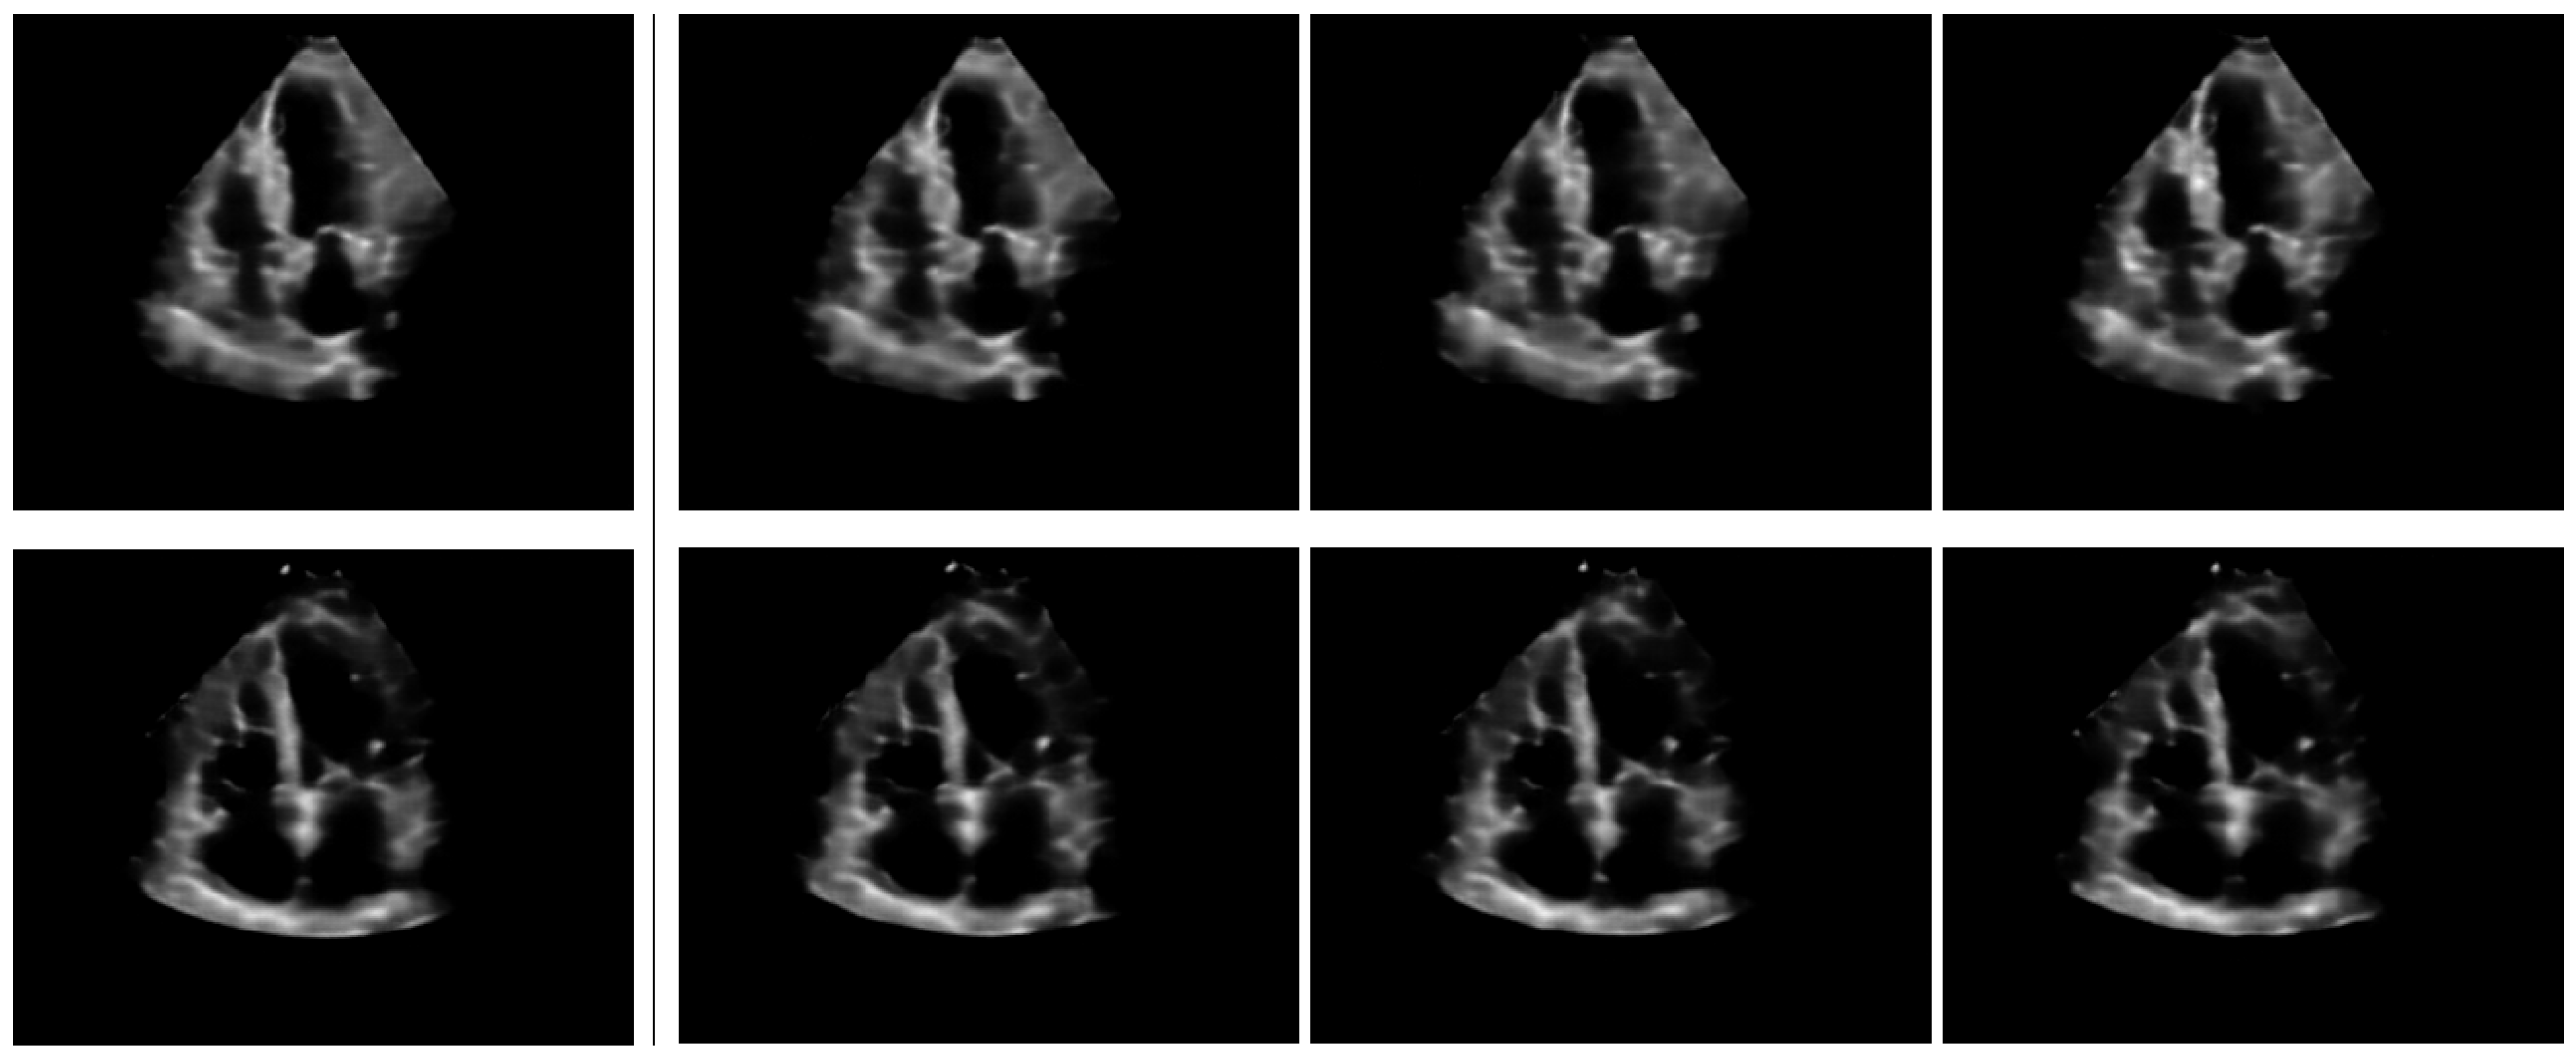

To qualitatively evaluate the impact of modifier concepts, the greedy concept map of the middle image of Figure 3 is modified in two ways, by swapping 2 modifier and 2 normal concepts: first, (i) the modifier concepts and are swapped and the image is reconstructed without any style component (); and (ii) starting from the greedy map, concepts and are now swapped and the image is reconstructed in the same manner (with ). The effects are illustrated in Figure 4: in the former case only minor shape modifications are observed around the grid locations where concept swaps were done. In the latter case, the effect is more significant, as it appears that the LV free wall changed place with the septum.

Figure 4.

Effect of concept swapping. The left image is the reconstruction based only on the greedy concept map (with ). The middle reconstruction illustrates the effect of swapping 2 modifier concepts, while the right reconstruction illustrates big changes induced by swapping two anatomy-specific concepts.

While modifier concepts seem to function primarily in a styling role, it is important to note that the Feature Decoder block processes regions of adjacent concept locations to reconstruct the low-level image features . This means that neighboring concepts cooperate to form larger and more complex anatomical structures. Modifier concepts are not devoid of semantic meaning, as our experiments showed that replacing a specialized anatomical concept like with a modifier concept still yields similar reconstructions, albeit with slight alterations in shape and/or region brightness patterns. Additionally, although reconstructing images based solely on may produce rough outlines of echocardiographies, suggesting that concepts only encode basic brightness blobs, we later show that the concept probability grid contains rich semantics that can be used in tasks such as instance retrieval (Section 5.1).